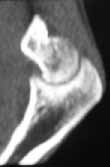

17 y/o female, had supracondylar elbow fracture in childhood which was treated by closed reduction and fixation with K-wires.

Now has elbow ROM 30-90 deg. Complaind moderate pain during activity.

I would not attempt to do anything arthroscopically here. There is much too much distortion of anatomy. I don't believe you will get her a greater arc of motion by any means. Her distal humerus is far too distorted and has developed that way. Her capitellum appears malaligned, pointing more distally than usual which is probably limiting her flexion, andthere is deformity to the ulnohumeral joint. The osteophytes are secondary, and removal may decrease some of her pain at the terminus of extension/flexion, but won't change her motion. Her arc of motion can be changed to allow her EITHER more flexionOR more extension, if an osteotomy is done, for instance- it might be moved to 60-120, or to 0-60 (not particularly functional). An osteotomy to correct the varus deformity will be cosmetic only, and one must be careful of injuring the median nerve.